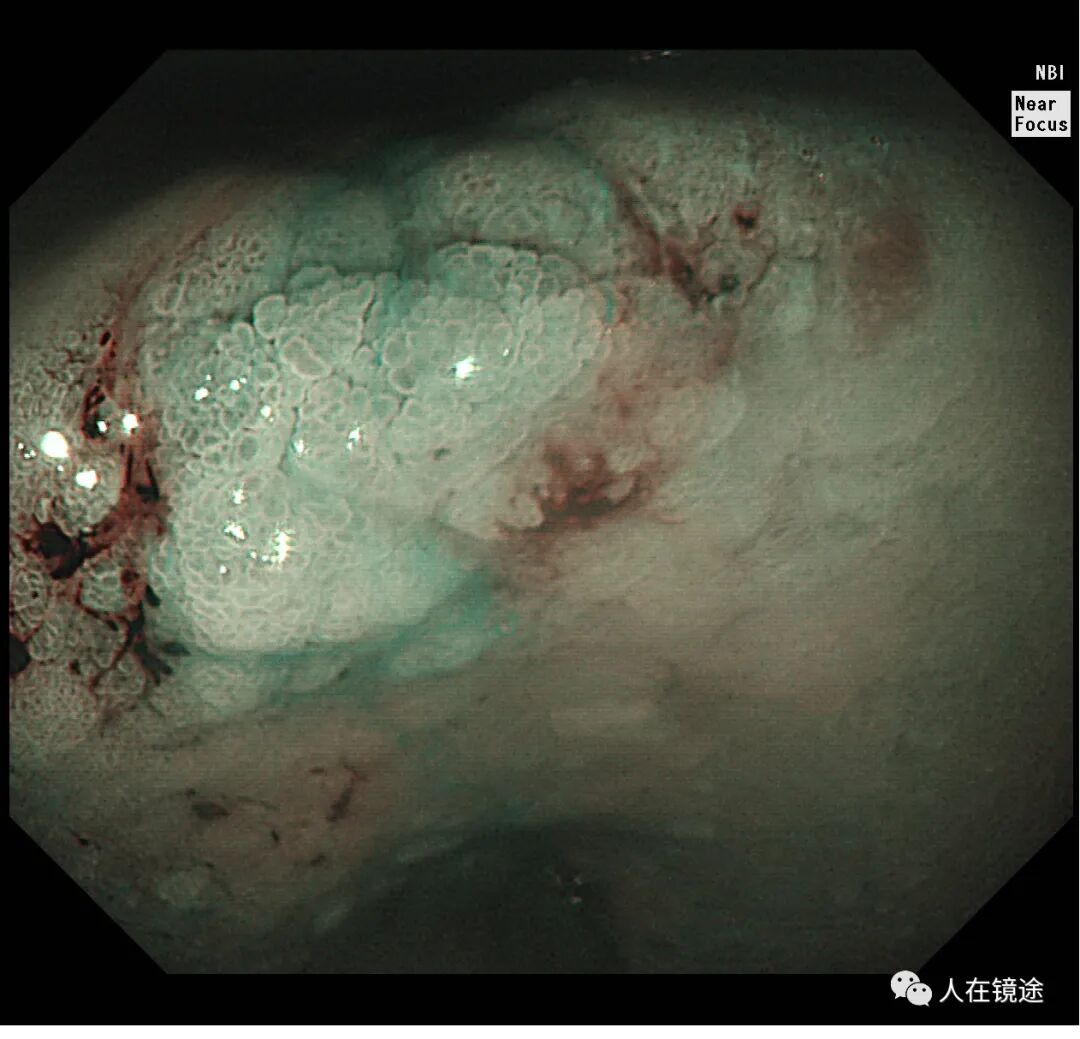

NBI+近焦示:胃窦小弯见一0.8*1.2cmIIa粘膜发病变呈咖色,边界清楚,微结构紊乱,表面粘膜高低不平伴自发性出血